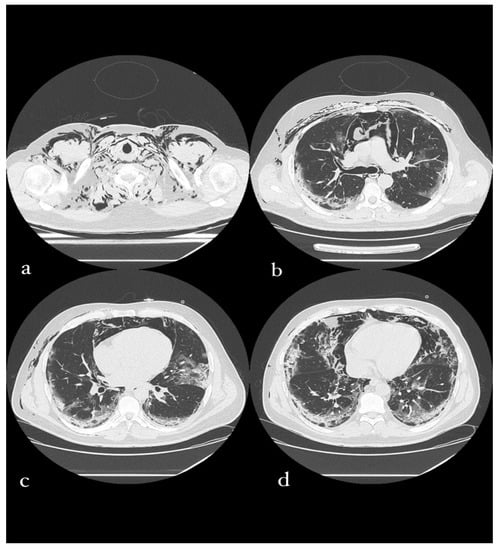

3.6.2. CT Imaging Findings

Diffuse subcutaneous emphysema in the cervical and parietal-costal region is more anteriorly marked. There was also massive pneumomediastinum and thin anterior apical PNX flap on the right.

Evidence of multiple areoles of GGO-type densitometric increase with associated thickening of the interlobular septa from crazy paving was found in both lungs, predominantly subpleural. There are multiple fibrotic striae with a course parallel to the pleura, more evident in the lower lobes. No significant ilo-mediastinal adenomegalies and no pleural effusion were reported (Figure 6).

Figure 6. A 49-year-old male patient in whom massive invasive ventilation resulted in the formation of pneumomediastinum. The formation of pneumomediastinum is due to traumatic rupture of the alveoli (caused by invasive ventilation), a phenomenon known as the Macklin effect. Subcutaneous emphysema can also be seen.